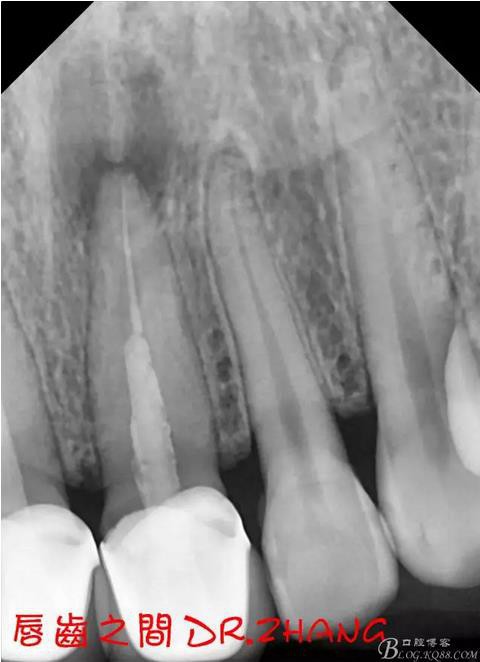

X片示11 21根管內(nèi)有高密度陰影 根尖低密度陰影

診斷:11 21慢性根尖炎

處理:21從修復(fù)體舌側(cè)打開通路 髓腔內(nèi)疑似纖維樁 高速和低速手機聯(lián)合去除樁核 在處理的過程中不斷拍片確認方向 去除樁核后拔髓針去除牙膠 只有一個標尖 膿液大量滲出 雙氧水和鹽水交替沖洗后 滲出減少 開放髓腔 隔日復(fù)診